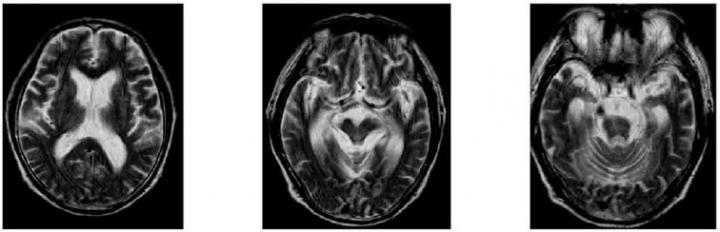

A team of Japanese researchers investigated patients whose symptoms resembled not only PSP but also Alzheimer's disease. Despite similarities in the symptoms, detailed pathological analyses showed no resemblance to either disease, which prompted the team to further research the new disease's underlying mechanism.

An autopsy done on one of the family members with the BSN mutation showed an accumulation of a protein called tau in the brain, which is not seen in a normal brain. The researchers believe that the BSN mutation is involved in the tau accumulation, which could cause the development of PSP-like symptoms. An experiment introducing a mutated rat BSN gene to cultured cells also suggested that the mutation causes the accumulation of tau. Communication between nerve fibres could also be affected, as BSN protein play a role in it.